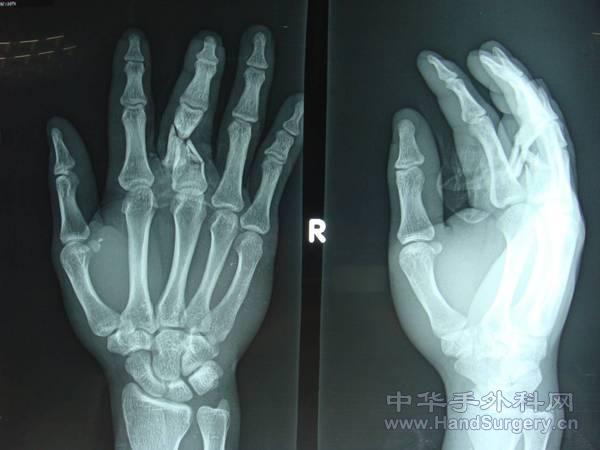

术中用克氏针交叉固定后,将碎小的骨块钻孔后,用无损伤线缝合固定,